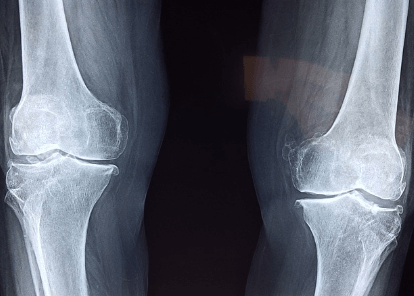

콘드로이친은 연골을 구성하는 성분 중 하나로, 관절 건강에 도움을 주는 성분으로 알려져 있습니다. 쉽게 말하면 관절 사이에서 윤활유 역할을 한다고 이해하면 되겠습니다.

콘드로이친은 연골세포를 보호해 주는 성분입니다. 나이가 들어감에 따라 연골이 닳는데요. 콘드로이친은 연골 조직을 보호하고 강도를 유지하고 강도를 유지하는 역할을 합니다. 이러한 기능에 따라 연골 보호에 큰 도움을 주는 것으로 알려져 있습니다.

콘드로이친은 연골 조직을 재생하는데 도움을 줍니다. 연골의 손상된 조직을 재생시키고 회복하는데 도움을 줘서 관절 건강을 개선하는 역할을 합니다.

콘드로이친은 보행능력을 개선시켜 줍니다. 나이가 들면 관절염과 같은 질환 때문에 보행능력이 점차 저하됩니다. 콘드로이친을 복용하면 관절 건강과 연골 조직을 보호하는 역할을 하기 때문에 보행 능력이 개선됩니다.

콘드로이친은 관절 건강에 도움을 줍니다. 나이가 들어감에 따라 연골이 닳게 되고 보행 시 관절 통증을 호소하게 됩니다. 콘드로이친은 손상된 연골을 재생시키는 역할을 하기 때문에 관절 건강을 유지시키고 관절 통증을 예방하는데 도움을 줍니다.